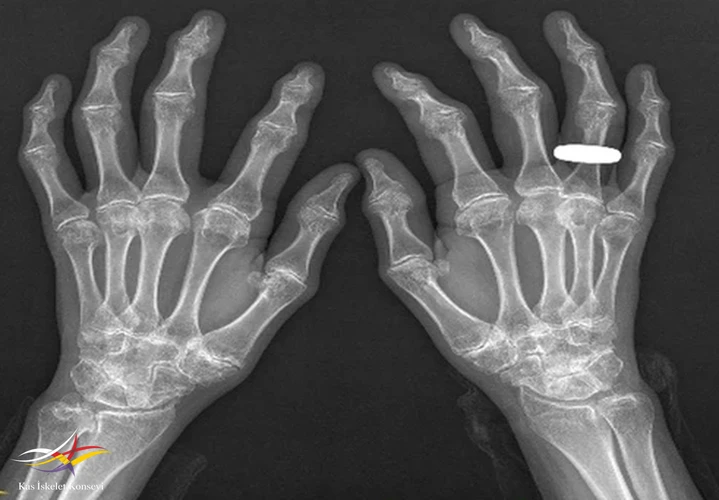

Resim 3.

Muayene: Fizik muayenede omuz, el bilek,dirsek, kalça, ayak bilek rom kısıtlı. El PIF'lerde şişlik, büyümüş kemiksi eklem görünümü? Boy kısa, kifotik görünüm mevcut? Artrit yok, ateş, kilo kaybı,oral aft genital ülser, ağız göz kuruluğu, Raynauld fenomeni yok.

İncelemeler: Biokimyasal tetkikler normal, RF VE ANTİ CCP (-).

2. Epifizyal değişiklikler: Uzun kemiklerin epifizlerinde irregular yapı, morfolojisi bozulmuş epifizler.